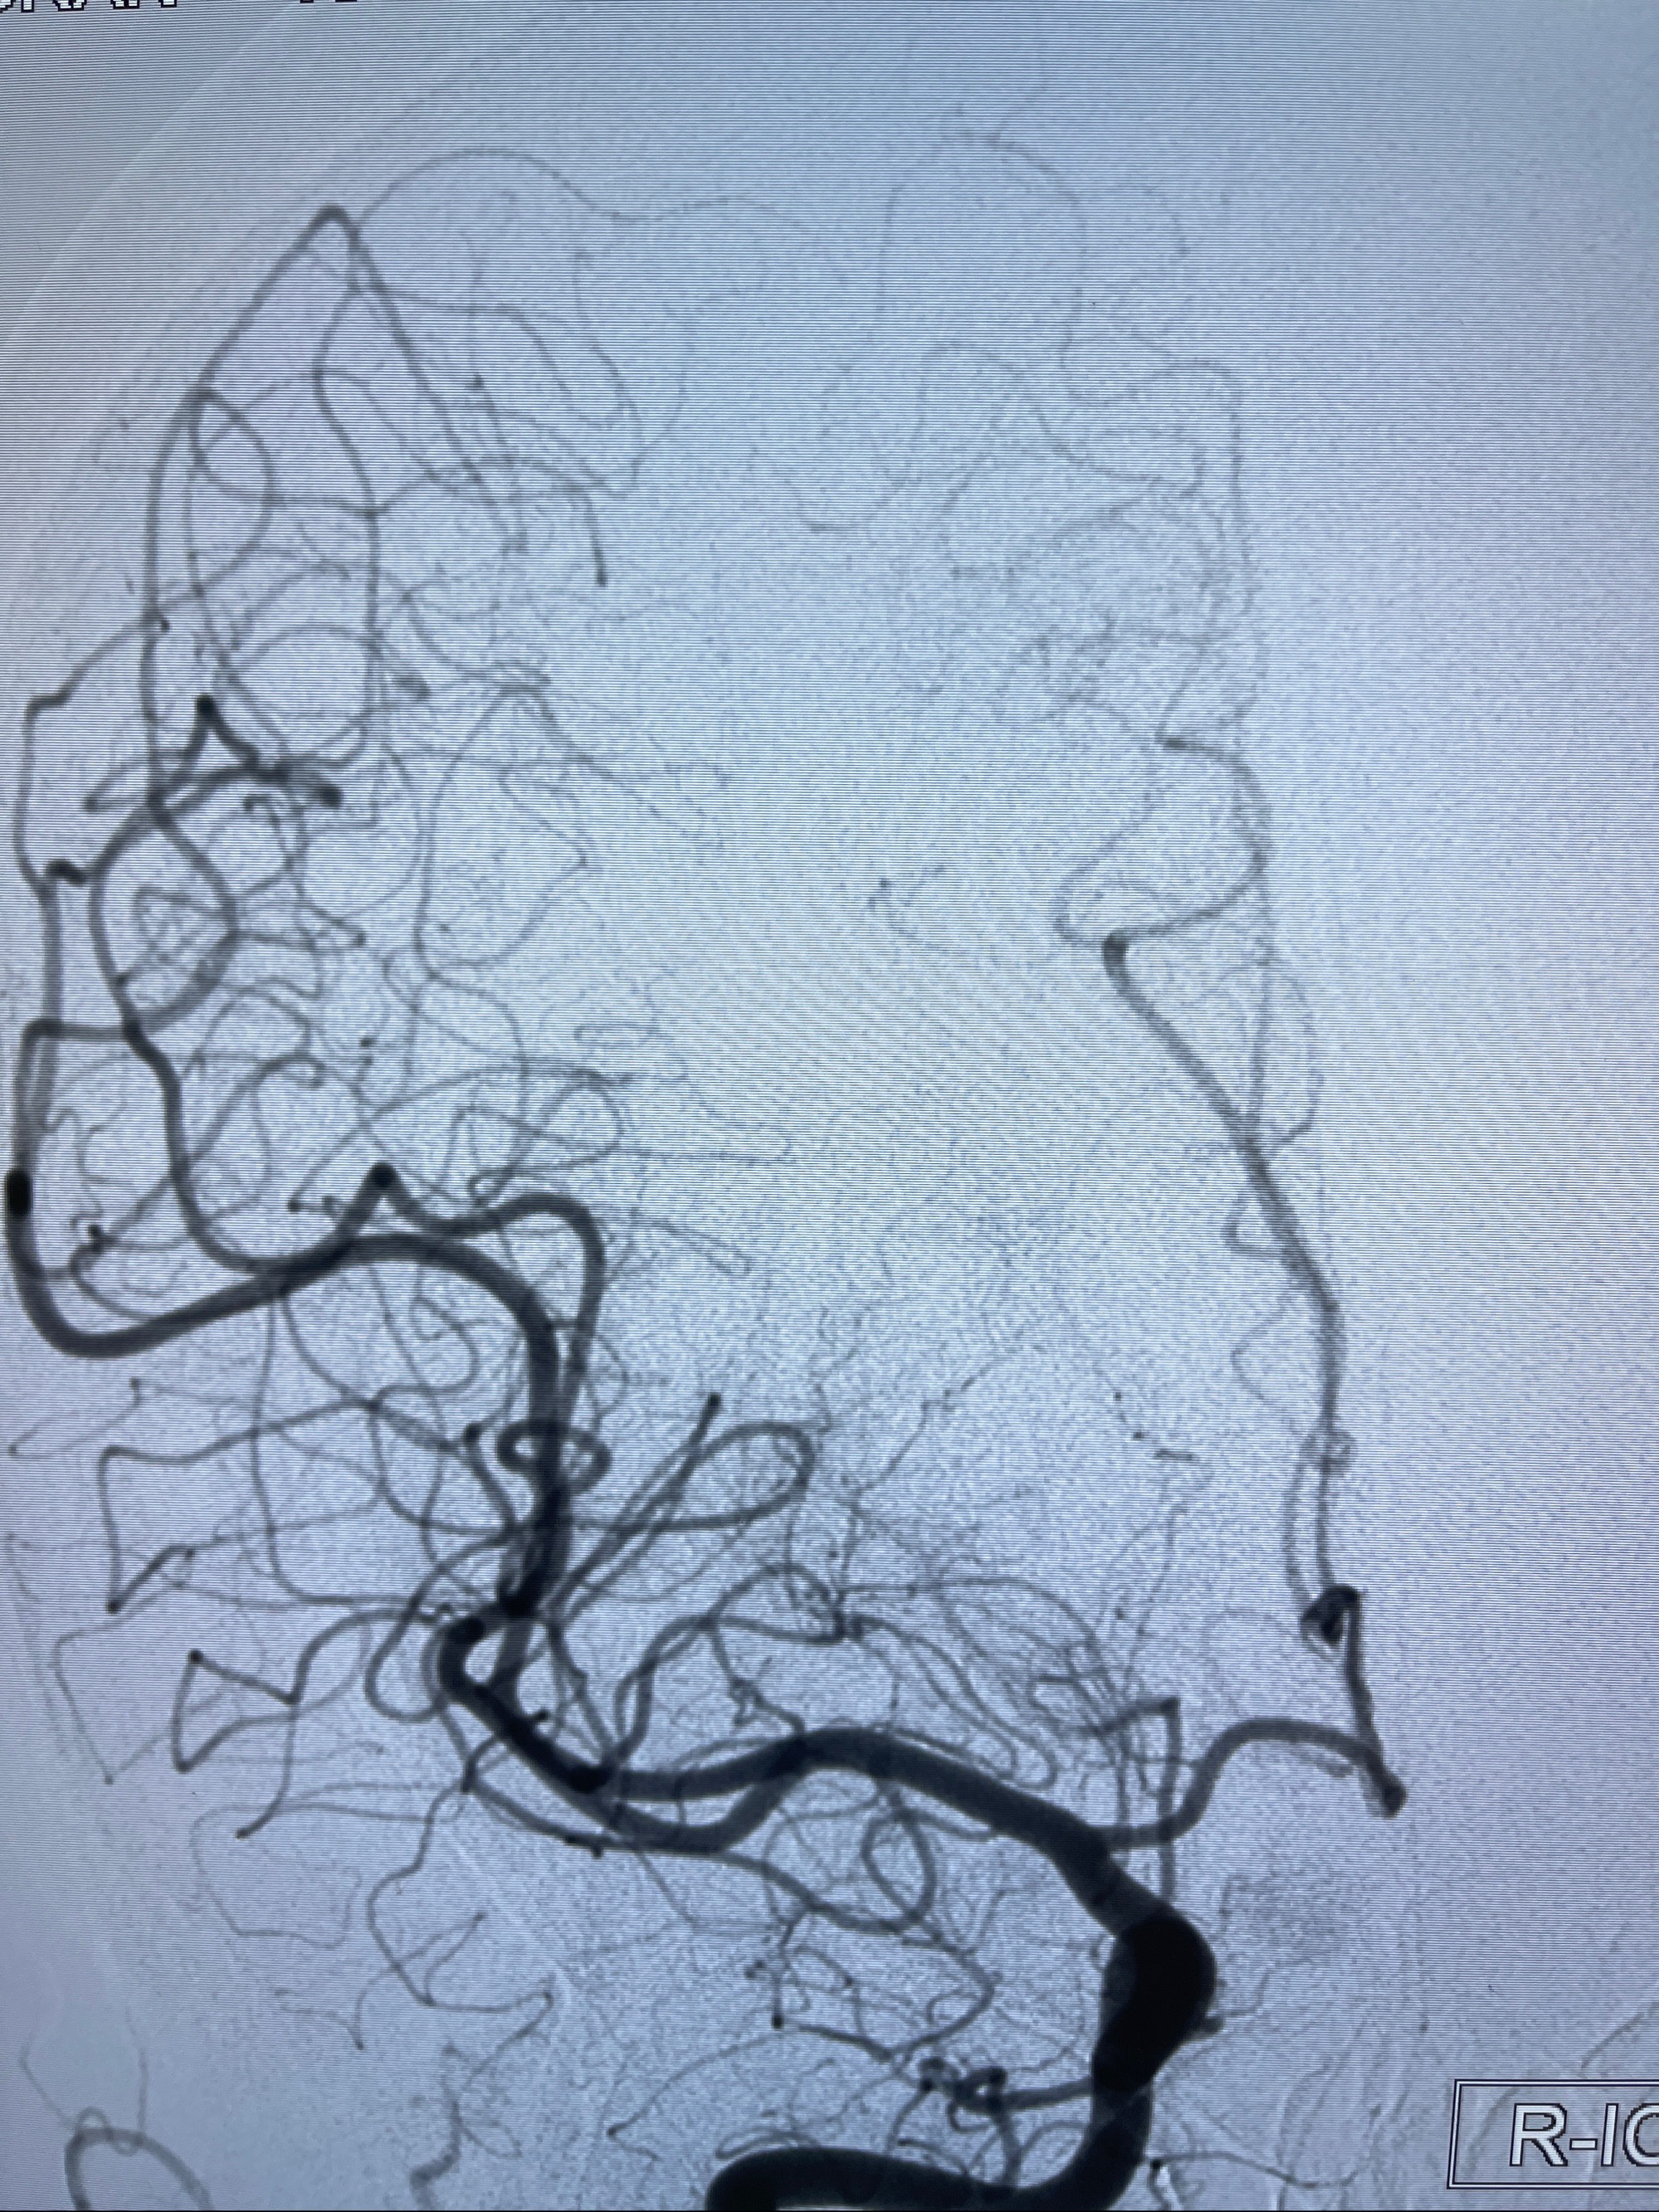

2023-08-30DSA:左侧颈内动脉眼动脉动脉瘤,约3*9.2*7.3mm大小

2023-09-06全麻下行左侧颈眼动脉瘤

密网支架辅助栓塞